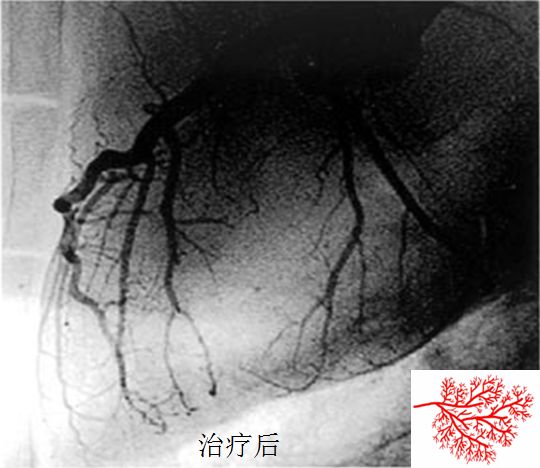

CSWT是利用超声定位,依靠心电图门控技术触发,通过仪器下端的水垫及超声耦合剂,向设定的心脏治疗靶区域释放脉冲式声能量(震波),以抑制缺血相关的细胞损伤,促进缺血区域的毛细血管生成、微循环重建。